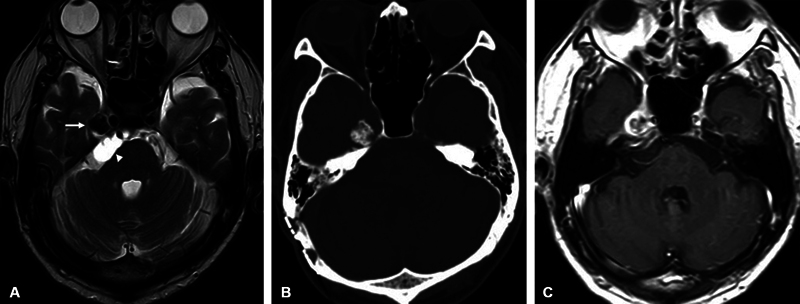

神经轴钙化假性肿瘤(CAPNON)是罕见的非肿瘤性钙化病变,可发生在整个神经轴。颅底病变可累及脑神经。手术切除通常预后良好,相关文献仅报道少数复发病例。我们经历了一例Meckel's cave的CAPNON复发病例,在最初切除病变的囊性部分后,CAPNON延伸到桥小脑池并累及三叉神经。48岁男性,右侧上睑下垂4年。磁共振成像显示在Meckel洞内出现钙化病变,伴囊性病变延伸至桥脑小脑池。病变的囊性部分在初始手术中使用右侧枕下外侧入路切除。然而,囊性病变在23个月内恢复到术前大小。在切除过程中,采用右侧硬膜外颞下入路成功切除右侧Meckel腔内钙化肿块和延伸至右侧桥小脑池的囊性病变。术后患者神经系统症状消失。组织病理学检查发现CAPNON。本报告描述一例罕见的Meckel洞穴CAPNON病例,具有独特的临床病程。第一次手术后,桥小脑池囊性病变复发,但第二次手术成功治疗。

Calcifying pseudoneoplasms of the neuraxis (CAPNON) are rare non-neoplastic calcified lesions that can occur throughout the entire neuraxis. Cranial nerves may be involved in skull base lesions. Surgical resection usually has a good prognosis, with only a few cases of recurrence reported in the relevant literature. We experienced a recurrent case of CAPNON in Meckel's cave extending to the cerebellopontine cistern with involvement of the trigeminal nerve after initial resection of the cystic part of the lesion. A 48-year-old man presented with a 4-year history of right-sided ptosis. Magnetic resonance imaging revealed a calcified lesion arising in Meckel's cave, with a cystic lesion extending to the cerebellopontine cistern. The cystic part of the lesion was excised during the initial surgery using the right lateral suboccipital approach. However, the cystic lesion regrew to its preoperative size within 23 months. The right extradural subtemporal approach was used to successfully remove both the calcified mass in the right Meckel cave and the cystic lesion extending to the right cerebellopontine cistern during the resection of the lesion. The patient's neurological symptoms resolved postoperatively. CAPNON was identified during the histopathological examination. This report describes a rare case of CAPNON in Meckel's cave with a unique clinical course. After the first operation, cystic lesions recurred in the cerebellopontine cistern, but they were successfully treated by a second operation.